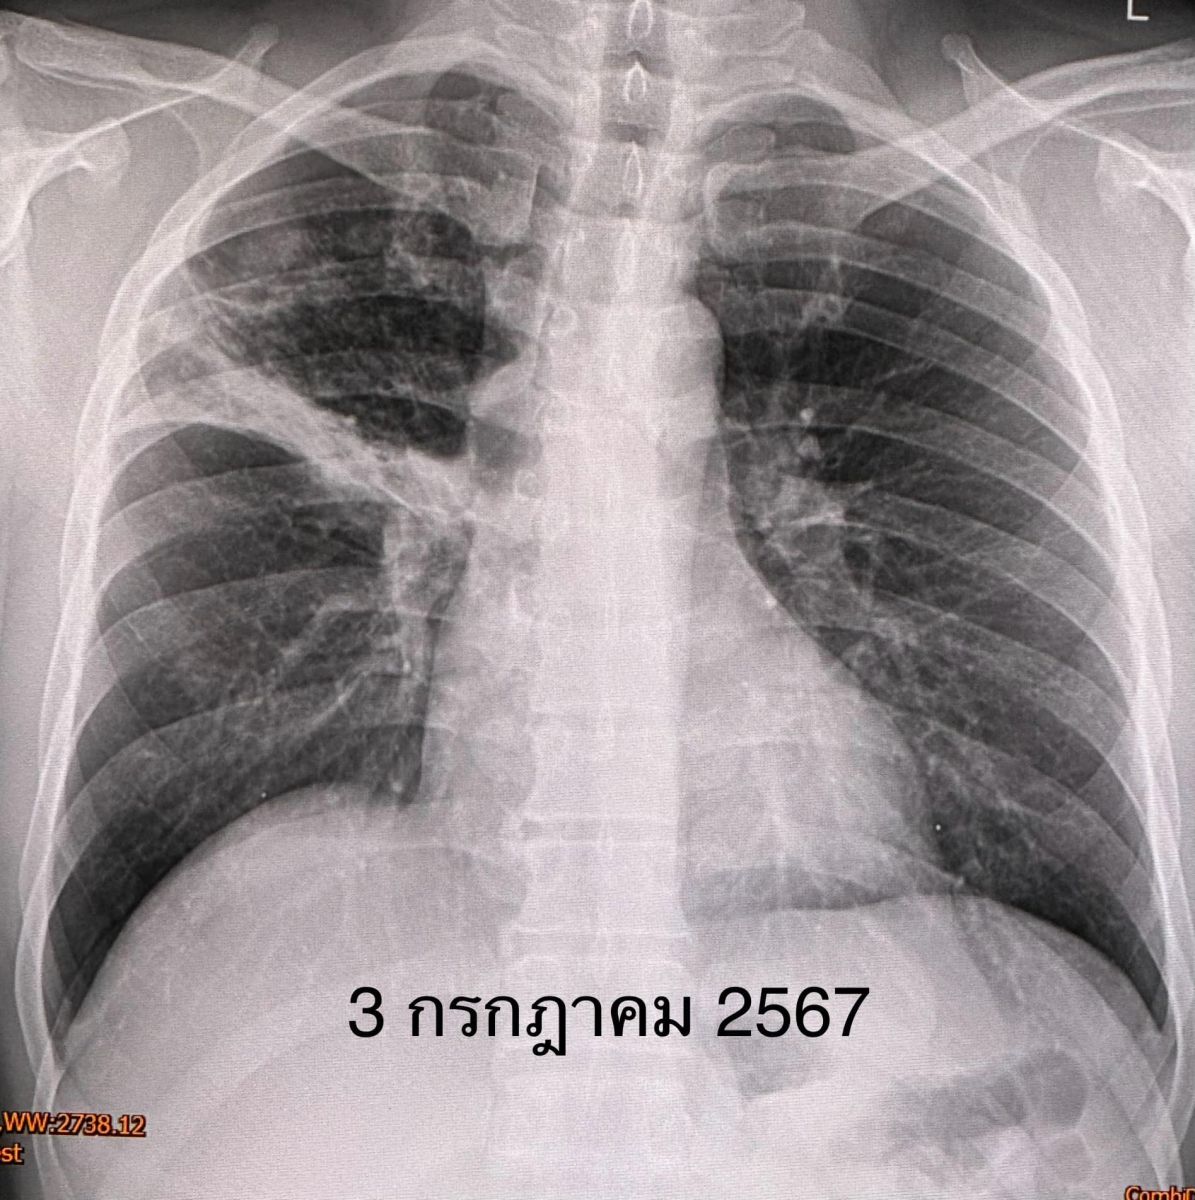

ผลการตรวจร่างกาย อุณหภูมิ 38.5 องศาเซลเซียส น้ำหนัก 88 กิโลกรัม ต่อมน้ำเหลืองที่คอไม่โต ฟังปอดปกติ เอกซเรย์ปอดมีฝ้าขาวที่ปอดข้างขวาด้านบน ตรวจเลือดไม่พบติดเชื้อ HIV ส่งเสมหะย้อมเชื้อหาวัณโรค AFB smear ให้ผลบวก ส่งเสมหะตรวจรหัสพันธุกรรมของเชื้อวัณโรค พบเชื้อวัณโรค M.tuberculosis ไม่ดื้อยา rifampicin ได้ผลในเวลาไม่กี่ชั่วโมง

แพทย์วินิจฉัย ว่าเป็นวัณโรคปอด เริ่มยารักษาวัณโรค 4 ขนานคือ INH, rifampicin, pyrazinamide, ethambutol และวิตามิน B6 ผู้ป่วยกินยาได้ ไม่แพ้ยา หลังกินยาไข้ลง ไม่ไอ ไม่มีเสมหะ ผลเพาะเชื้อวัณโรค 1 เดือนต่อมา ขึ้นเชื้อวัณโรค M.tuberculosis ไวต่อยารักษาวัณโรคทุกตัว เอกซเรย์ปอดหลังได้รับยา 5 สัปดาห์ ฝ้าขาวที่ปอดข้างขวาด้านบนดีขึ้น ต้องให้ยารักษาวัณโรค 4 ขนานต่อไปจนครบ 2 เดือน แล้วลดยาเหลือ INH, rifampicin และวิตามิน B6 รับประทานต่อไปจนครบ 6 เดือน